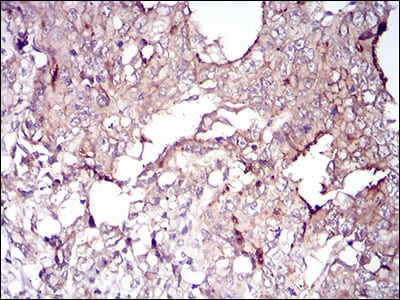

- Immunohistochemical analysis of paraffin-embedded human muscle tissues using VIL1 mouse mAb with DAB staining.

- Immunohistochemical analysis of paraffin-embedded human stomach cancer tissues using VIL1 mouse mAb with DAB staining.